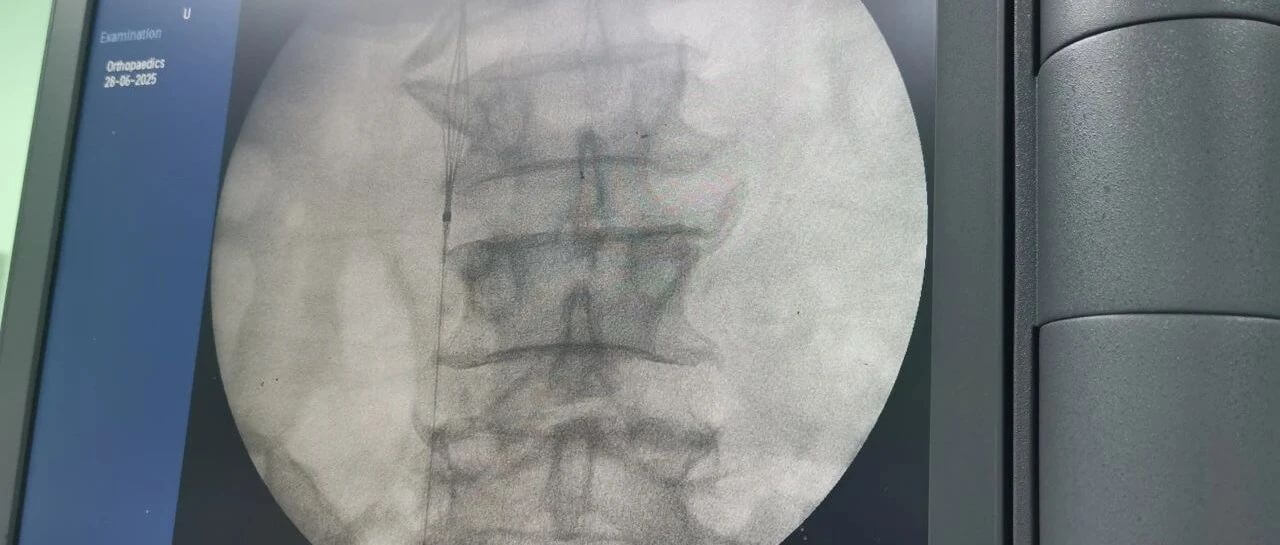

面對這一嚴(yán)峻挑戰(zhàn),羅軍副院長團(tuán)隊(duì)果斷決策,先行實(shí)施“下腔靜脈濾器植入術(shù)”。手術(shù)團(tuán)隊(duì)?wèi){借精湛的技術(shù),在患者的下腔靜脈(人體最大的靜脈干)內(nèi)精準(zhǔn)放置了一個特殊的“濾網(wǎng)”裝置——腔靜脈濾器。它的核心作用就是充當(dāng)“血栓攔截網(wǎng)”:

保障后續(xù)手術(shù)安全:為接下來必須進(jìn)行的、耗時較長的骨盆髖臼粉碎性骨折修復(fù)手術(shù)(尤其是利用3D打印技術(shù)進(jìn)行的精準(zhǔn)手術(shù))掃除了最大的安全隱患,提供了至關(guān)重要的手術(shù)安全保障期。